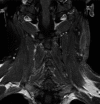

Background: Cervical schwannoma is a rare neoplasm that usually occurs like a nondolent lateral neck mass but when growing and symptomatic requires radical excision. Sodium fluorescein (SF) is a dye that is uptake by schwannomas, which makes it amenable for its use in the resection of difficult or recurrent cases.

Methods: We describe the case of a patient presenting with a recurrence of a vagus nerve schwannoma in the cervical region and the step-by-step technique for its complete microsurgical exeresis helped by the use of SF dye.

Results: We achieved a complete microsurgical exeresis, despite the presence of exuberant perilesional fibrosis, by exploiting the ability of SF to stain the schwannoma and nearby tissues. That happens due to altered vascular permeability, allowing us to better differentiate the lesion boundaries and reactive scar tissue under microscope visualization (YELLOW 560 nm filter).

Conclusion: Recurrent cervical schwannoma might represent a surgical challenge due to its relation to the nerve, main cervical vessels, and the scar tissue encompassing the lesion. Although SF can cross both blood-brain and blood-tumor barriers, the impregnation of neoplastic tissue is still greater than that of nonneoplastic peripheric tissues. Such behavior may facilitate a safer removal of this kind of lesion while respecting contiguous anatomical structures.